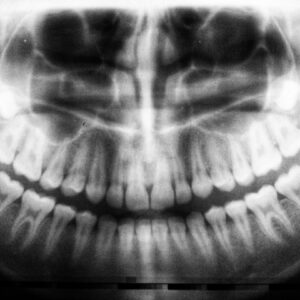

Photo Tooth X-ray

Tooth Decay On X Ray

Tooth decay, also known as dental caries, is a common yet serious condition that affects individuals of all ages. It occurs when the enamel, the hard outer layer of your…